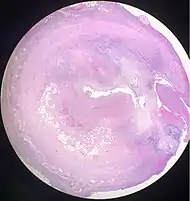

| An acutely inflamed and enlarged appendix, sliced lengthwise. | |

Micrograph of appendicitis showing neutrophils in the muscularis propria. H&E stain Acute suppurative appendicitis with perforation (at right). H&E stain

Acute suppurative appendicitis with perforation (at right). H&E stain